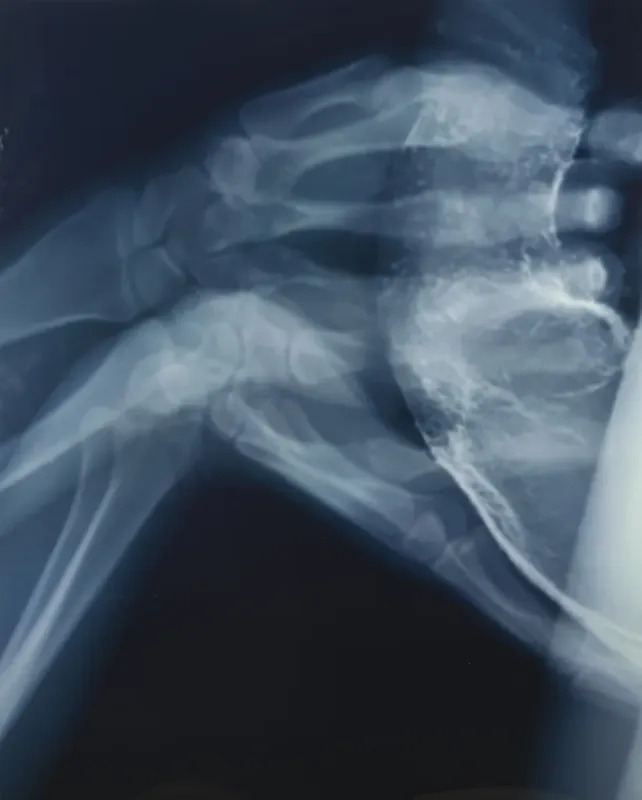

«Труба 1», Вим Дельвуа

Оценочная стоимость: £6–8 тыс.

«Труба 1» — это кардинально новый формат современного эротического искусства. Бельгийский неоконцептуальный художник-провокатор отличается от других деятелей искусства своим интересом к банальному, повседневному, китчевой культуре. Рентген-снимок орального полового акта демонстрирует этот процесс с совершенно новой, медицинской точки зрения, подобно иллюстрациям в студенческом учебнике. Насколько можно считать лот эротикой, вопрос субъективный, хотя новым видением современного искусства (главная цель которого, в большинстве своем, удивлять) — однозначно.